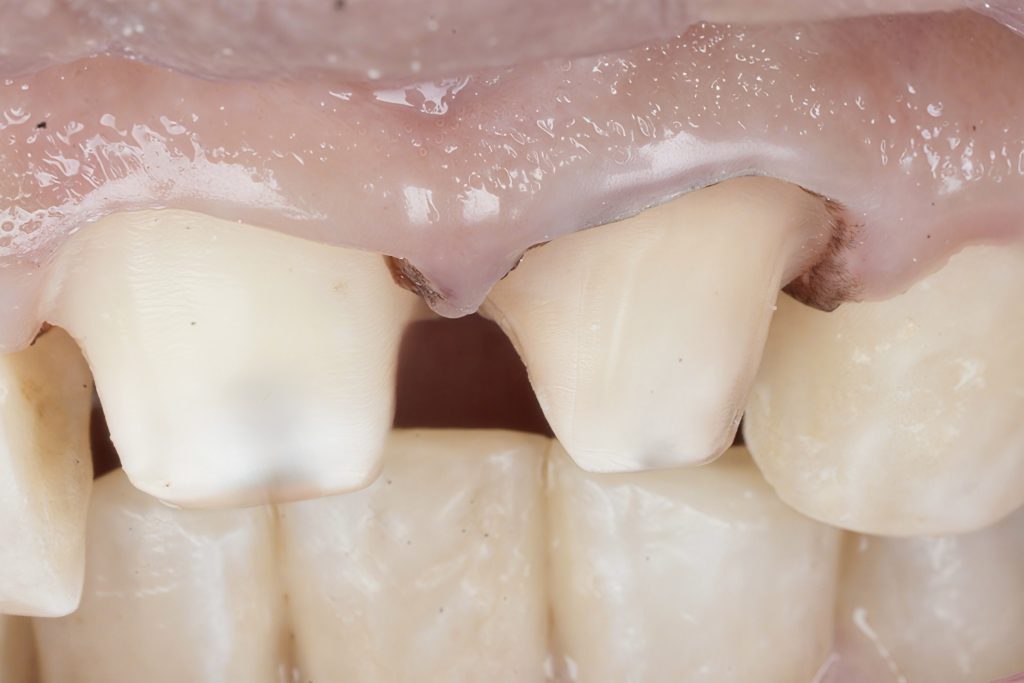

Step 3 — Conservative Emax Crown Preparation

All preparations were done under complete isolation.

- 1.0–1.2 mm labial reduction

- 1.5–2.0 mm incisal reduction

- Uniform chamfer finishing line

- Smooth internal contours

- Enamel preservation wherever possible

- Harmonized gingival zeniths

This ensured adequate thickness for lithium disilicate strength while preserving maximum tissue.